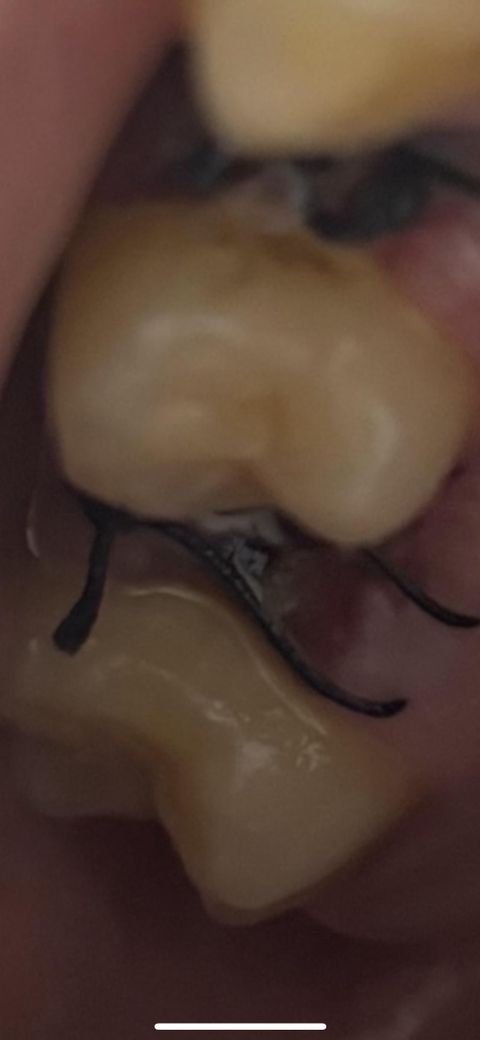

어금니 발치후 하얀색으로 번지는거는

어금니 발치후 꼬맸는데 하얀색으로 지금 번져있는데 이거 염증인가요? 새벽에는 조금 통증이 있고 낮에느 밤에는 없습니다 신경문제 같기도 하고

6일째인데 피맛도ㅠ나고 원래 이러나요?

하얀색으로 막이 덮이는 것은 정상적인 치유과정이며 통증이나 피도 미세하게 있을 수 있습니다.

1. 봉합실 주위의 흰색은 이물질, 음식물찌꺼기 같습니다. 해당 부위 물로 가볍게 가글해주세요.

2. 치유 과정 중에 염증, 육아조직이 생길 수 있습니다.

현재 사진상 염증으로 보이지는 않으며, 상처 치유과정에서 상처를 덮는 피막으로 자연스러운 현상이기에 걱정하지 않아도 됩니다. 하지만 발치부위에 염증이 생기지 않도록 소독용 헥사메딘 가글액으로 가글하고 술과 흡연은 피하길 권합니다.